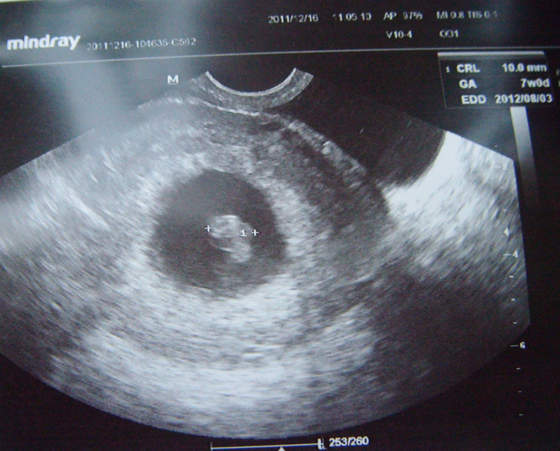

ufff, ja już po wizycie, serce waliło jak dzwon! Ale ulga.. zawsze to jeden stres w tym dziewięciomiesięcznym maratonie mniej :-) wróciłam od lekarza wczoraj po 22, i padłam nieżywa (wcześniej jeszcze prawie się porzygałam ale to chyba ze szczęścia ;-) ) następna wizyta 5 stycznia, no i padł szacunkowy termin porodu - 3 sierpnia - dla nas magicznie, Natka urodziła się 3 marca, mąż 3 kwietnia a ja 3 maja :-) i jak tu nie czuć magii Świąt... :-)

Bardzo się stresowałam, ale jest wszystko w porządku. Serduszko bije, dzieciaczek ma 10mm obecnie i jest idealnie 7 tydzień. Termin pokazuje (na zdjęciu po prawej u góry widać) perfect na 3 sierpnia.

Serduszko widzieliśmy, pulsowało, jest dobrze

Kolejna wizyta pod koniec stycznia, wtedy prawdopodobnie usłyszę serduszko, dzisiaj lekarz odradzał Dopplera. Powiedział, że lepiej nie faszerować dziecka promieniowaniem. Więc ok - zwłaszcza, że widać było to serduszko.

Załączam zdjęcie.